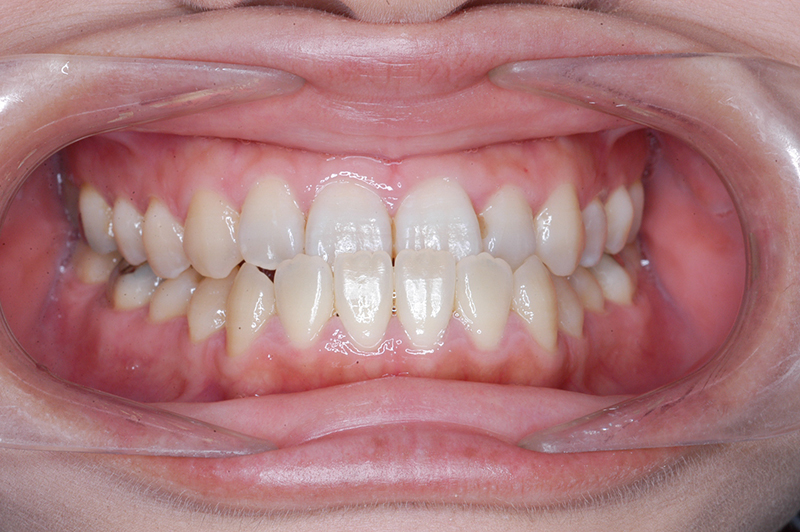

動的治療終了時

FP・IOP

批評・予后 ロウアングルのSkeletal Ⅲ級であり、下顎臼歯は近心傾斜しつつ7遠心部にはアップライトができるスペースがあると判断して、MEAWによる咬合平面の平坦化および可及的な下顎のカウンタークロックワイズローテーションによって改善を行うこととした。治療後には歯列の整直とⅠ級の咬合が得られた。(H30年9月現在で)保定開始4年経過しているが現在も咬合は安定している。